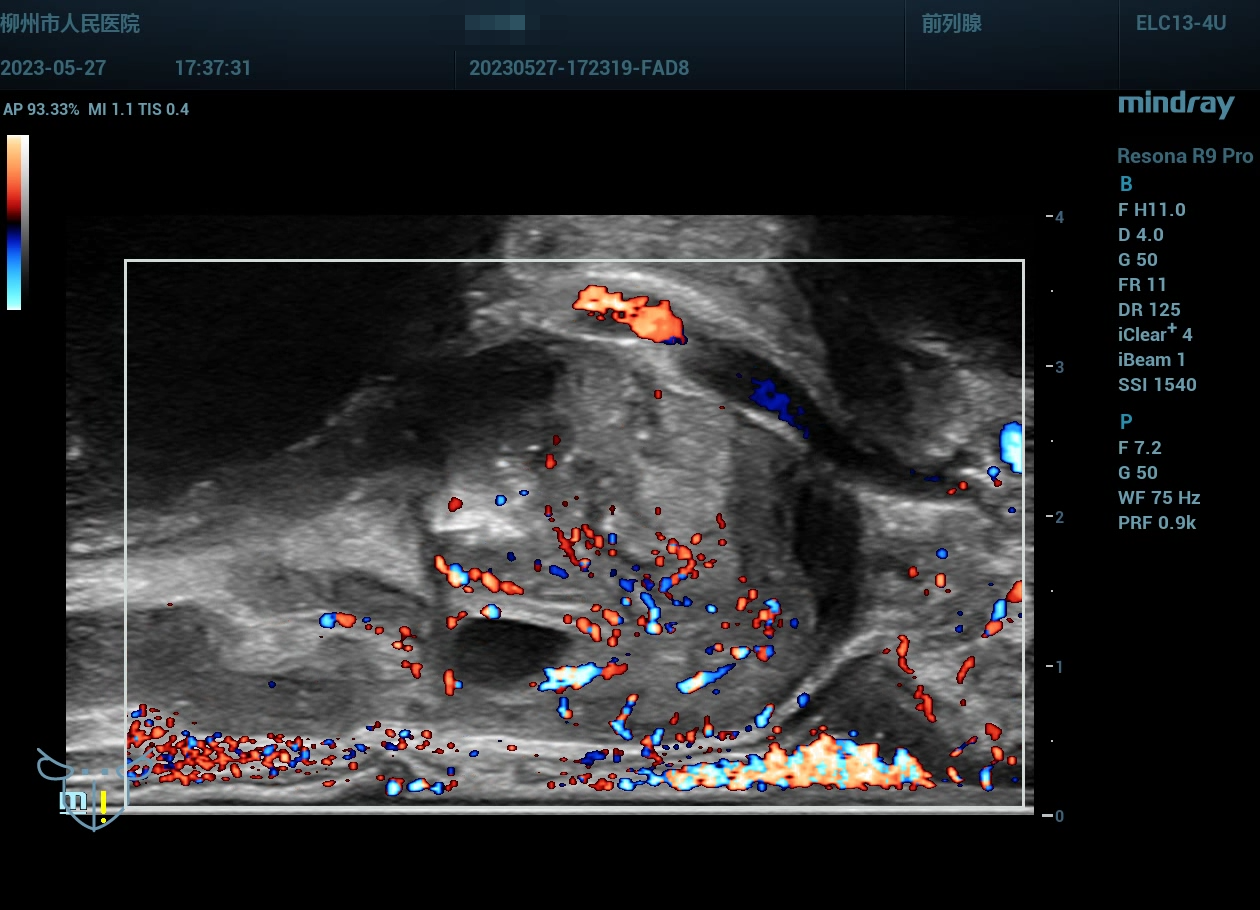

病史为年轻的男性,主要症状为尿痛、血精。

精囊腺的超声图像表现:肿胀、回声紊乱。